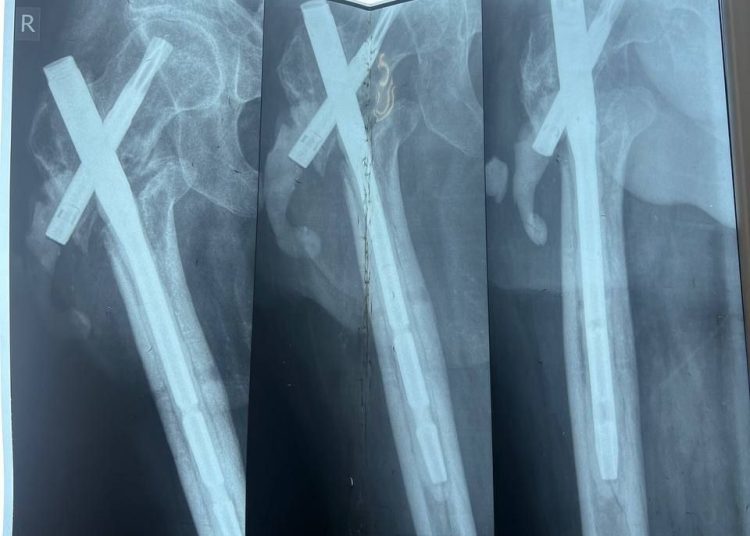

Пациентом стал 32-летний Илья из ЛНР, мобилизованный 25 февраля 2022 года.Сержант получил тяжелейшее осколочное ранение правого бедра под Херсоном 28 августа 2022 года.За три с половиной года боец прошёл через десять госпиталей, включая ЦВКГ им. Вишневского в Москве и ВМА им. Кирова в Санкт-Петербурге, перенёс множественные операции по удалению некрозов и остеосинтезу.

К моменту увольнения со службы в июле 2024 года основная проблема оставалась нерешённой: правая нога была короче левой почти на 9 сантиметров. Стандартное протезирование в такой ситуации неэффективно.

Хирургам ЛРКБ предстояло работать в рубцово-изменённых тканях после десятка предыдущих вмешательств, устранить очаги инфекции и с помощью специальных ревизионных компонентов восстановить биологическую ось конечности и вернуть ей физиологическую длину.